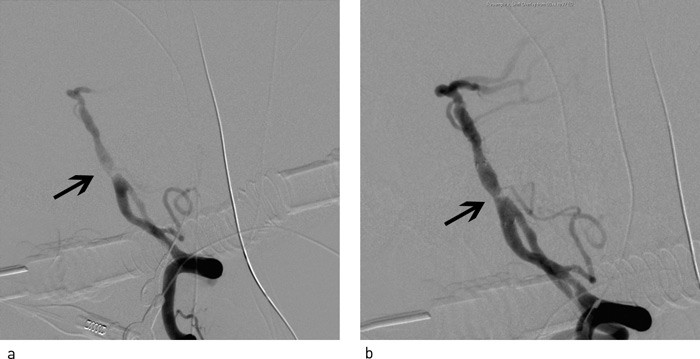

Ved cerebral angiografi ble det påvist akutt okklusjon av distale del av a. carotis interna på venstre side (carotis terminus) (fig 3a), manglende fremstilling av bakre a. comunicans posterior samt tynn første gren av høyre a. cerebri anterior. Begge carotisbifurkasjoner på halsen var normale. Ved hjelp av et trombektomikateter (MERCI-slynge, Concentric Medical Mountain View, California) ble venstre a. carotis interna, media og anterior åpnet opp (fig 3b, 3c, fig 4a, 4b). Blodgjennomstrømmingen til venstre hemisfære ble med angiografi verifisert gjenopprettet nesten tre og en halv time etter symptomdebut. Umiddelbart etter var pasienten noe mer våken og kunne med noe møye si navnet sitt (NIHSS 14). CT av hodet viste ingen blødning, men ødem i venstre hemisfære. CT dagen etter viste lavattenuerende forandringer i deler av a. cerebri medias forsyningsområde på venstre side. Han lå i flere dager i intensivavdeling. Ny vurdering angående hemikraniektomi ble aldri nødvendig. Pasienten ble overført til opptrening i slagenhet, der han fire uker etter prosedyren var i klinisk bedring.